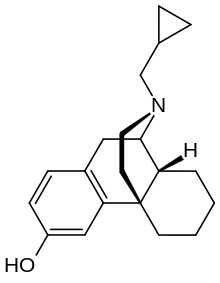

- 3-Hydroxymorphinan

- Cyclorphan

Cyclorphan Cyclorphan |